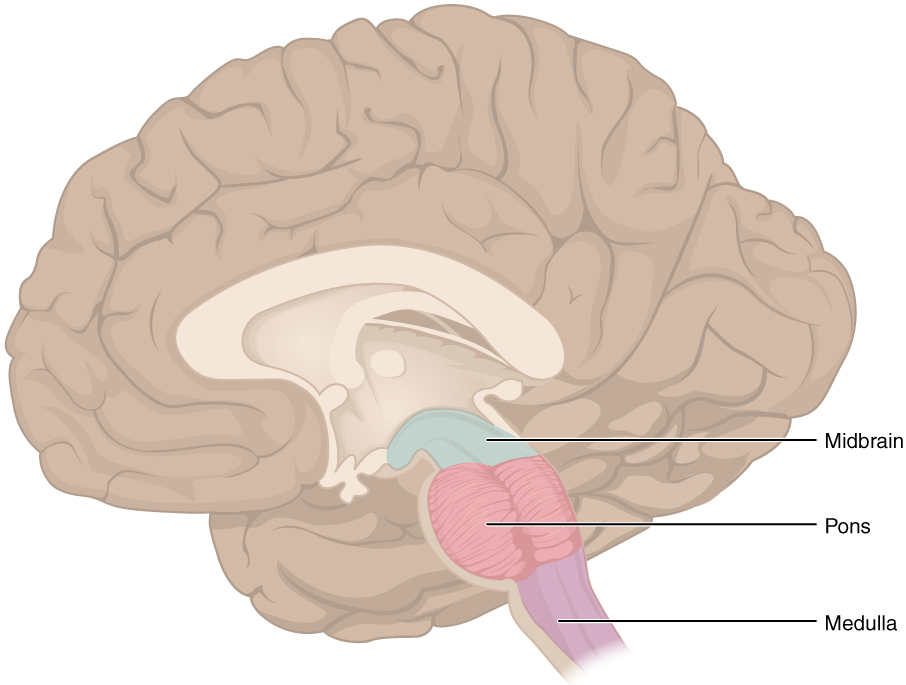

Medulla Oblongata: What It Is, Function & Anatomy

Know Your Brain: Medulla Oblongata

Medulla oblongata | Description, Anatomy, & Function | Britannica

The Anatomy of the Medulla Oblongata

The Medulla Oblongata - Internal Structure - Vasculature

Medulla Oblongata Location, Function, and Features

The Medulla Oblongata and Pons